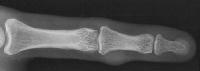

Xray shows a contour change of the middle phalanx deep to the tumor.

Click for larger image

Transillumination is indeterminate, slightly darker than surrounding tissues.